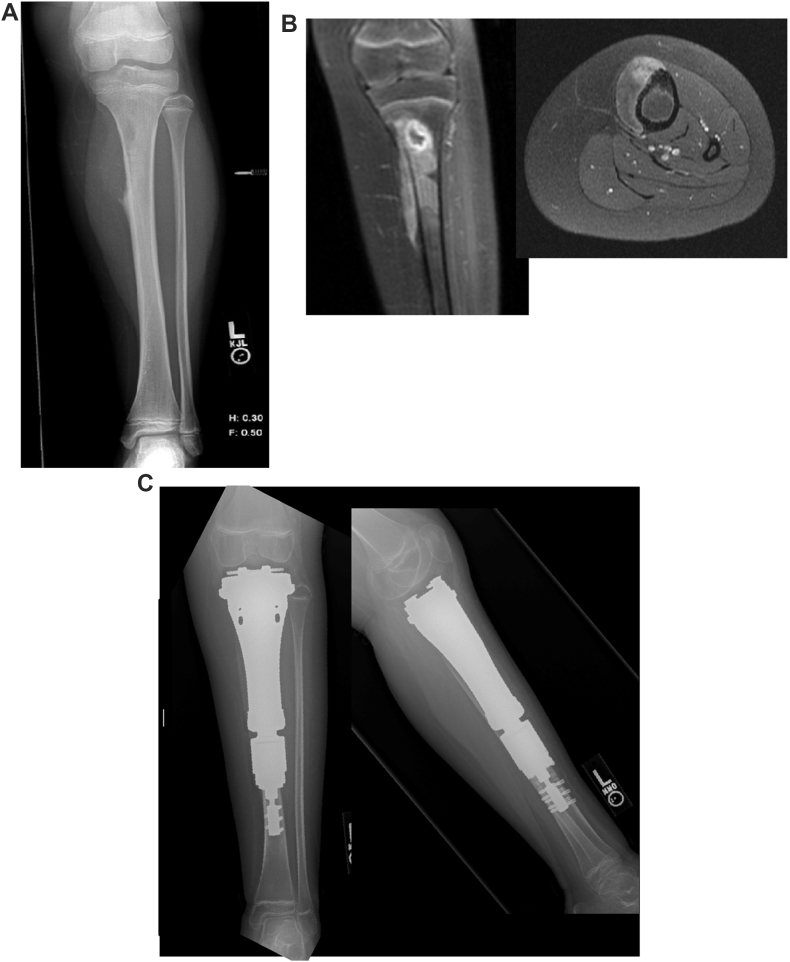

Background: Reconstruction of the proximal tibia following resection of malignant bone tumors in pediatric patients is traditionally limited to osteoarticular allografts or endoprostheses. Endoprostheses typically require resection or disruption of the distal femoral physis, which can lead to a leg length discrepancy (LLD). We introduce a novel form of proximal tibia limb reconstruction using a Compress® tibia hemiarthroplasty, which spares the distal femoral physis.

Methods: We retrospectively reviewed 5 patients who underwent proximal tibia osteosarcoma resection and reconstruction with a custom Compress® proximal tibia hemiarthroplasty. Data on function, survival, LLD, complications, and patient-reported outcomes were collected.

Results: Mean age at resection was 10.4 years [range: 8.8-12.9 years]. Mean implant survival was 59 months [range: 34-83 months]. One patient developed a deep infection, and two patients required implant lengthening. Both were later converted to a rotating hinged total knee arthroplasty (RHTKA) ​> ​58 months after index surgery. At the last follow-up, all living patients had knee range of motion from 0 to 110°, walked unassisted, and had no LLD or knee instability. Mean Toronto Extremity Salvage Score was 90 [range: 80-97].

Conclusions: Proximal tibia hemiarthroplasty reconstruction after tumor resection in skeletally immature patients preserves the distal femoral physis and may potentially reduce LLD and delay conversion to an RHTKA until after skeletal maturity.